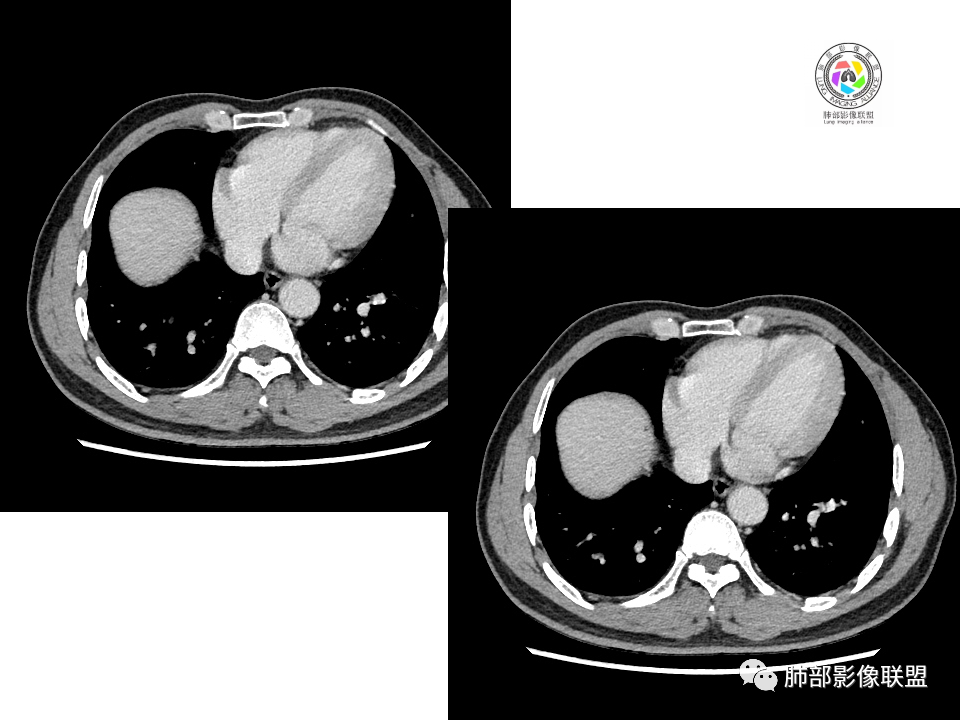

2.右肺下叶背段胸膜下块影,边界清楚光整,上下极见磨玻璃晕,未见明显分叶毛刺和棘状突起,未见胸膜凹陷或胸壁侵入。密度均匀,轻度不均匀强化。未见支气管进入。

3.右肺中叶外侧段胸膜下散在小片影,磨玻璃密度为主,边界不清,支气管相关。符合炎性特征!

4.右肺下叶基底段支气管血管束旁小结节影,边界清楚,强化不明显。注意,这结节在“遥远的”基底段。

右肺下叶占位,胸膜下,与胸膜关系密切;

密度均匀;糊墙,边缘膨隆为主;

部分血管推移。

血管也是稍推移,在边缘,病灶密度均匀,边缘稍收缩;均匀强化;

这两个病灶的密度、强化、形态、边缘、与血管的关系类似;还是一元论吧。